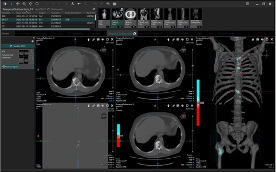

●EV Insite R

毎日の読影業務から研究,カンファレンスやインフォームドコンセントまで,さまざまな場面でEV Insite Rが活躍します。一貫した操作性と効率化された手順,豊富なカスタマイズ設定機能により,先生方一人一人の手に,目に,感覚になじむビューアです。

画像形態認識によるスライス位置合わせ

今回検査と過去検査の比較読影において,スライス位置を合わせる作業は煩雑になりがちですが,EV Insite Rでは画像の形態情報を基にスライス位置を自動で合わせることが可能です。CTとMR,フットファースト,ヘッドファーストなどの条件が異なっていても対応が可能です。

特長〈2〉

MPR

ビューアからワンクリックで高速にMPR作成が可能です。血管走行の確認などにおいてはCurved MPRの作成も行えますので,任意の角度での画像観察が可能です。